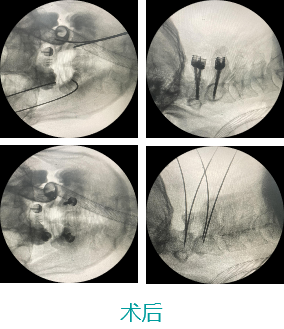

天玑II 辅助颈椎椎弓根螺钉内牢靠术

机械人辅助优势:天玑II传承精准智能,字斟句酌